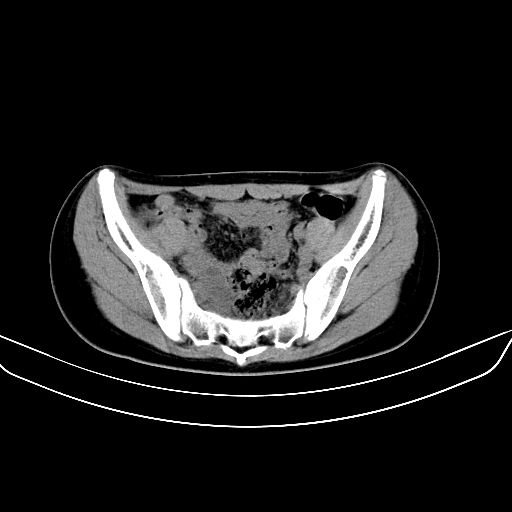

以下是引用zsl6918在2008-7-11 21:40:00的发言:[br]双侧骶髂关节骨质破坏以下三分之一为主,符合强直性脊柱炎表现

以下是引用zhangzhongshou在2008-7-11 21:41:00的发言:[br]患者是女性,hla-b27抗原(—),首先不太考虑强直性脊柱炎,建议查类风湿因子,骶髂关节改变考虑类风湿性关节炎可能性大,建议进一步检查。